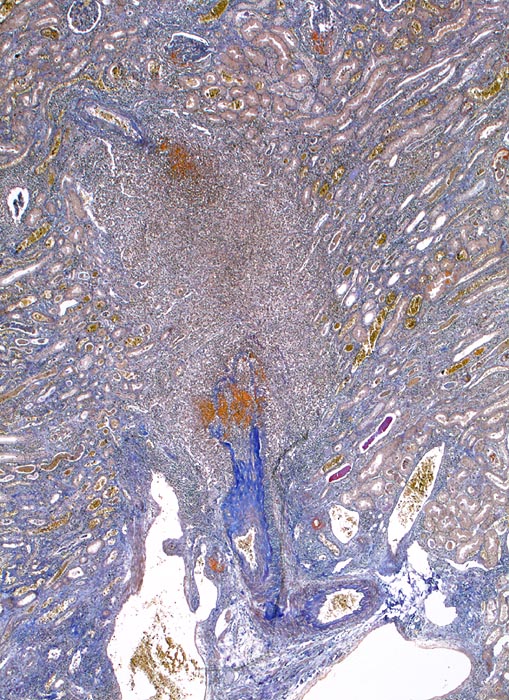

PathoPic – image database / PathoPic ID 5006 - extrakapilläre Glomerulonephritis bei Morbus Wegener

extrakapilläre Glomerulonephritis bei Morbus Wegener

Interlobäre Arterie mit sektorförmiger Nekrose begleitet von einem dichten Entzündungsinfiltrat.

Die Einbeziehung von Endstrecken der afferenten Arteriolen in die glomeruläre Nekrose ist häufig. Eine Vaskulitis der vorgeschalteten Gefässabschnitte wie in diesem Fall ist ungewöhnlich und passt eher zu einer Polyarteritis nodosa Makroform. Bei dieser Erkrankung sind die Glomerula aber definitionsgemäss nicht betroffen.